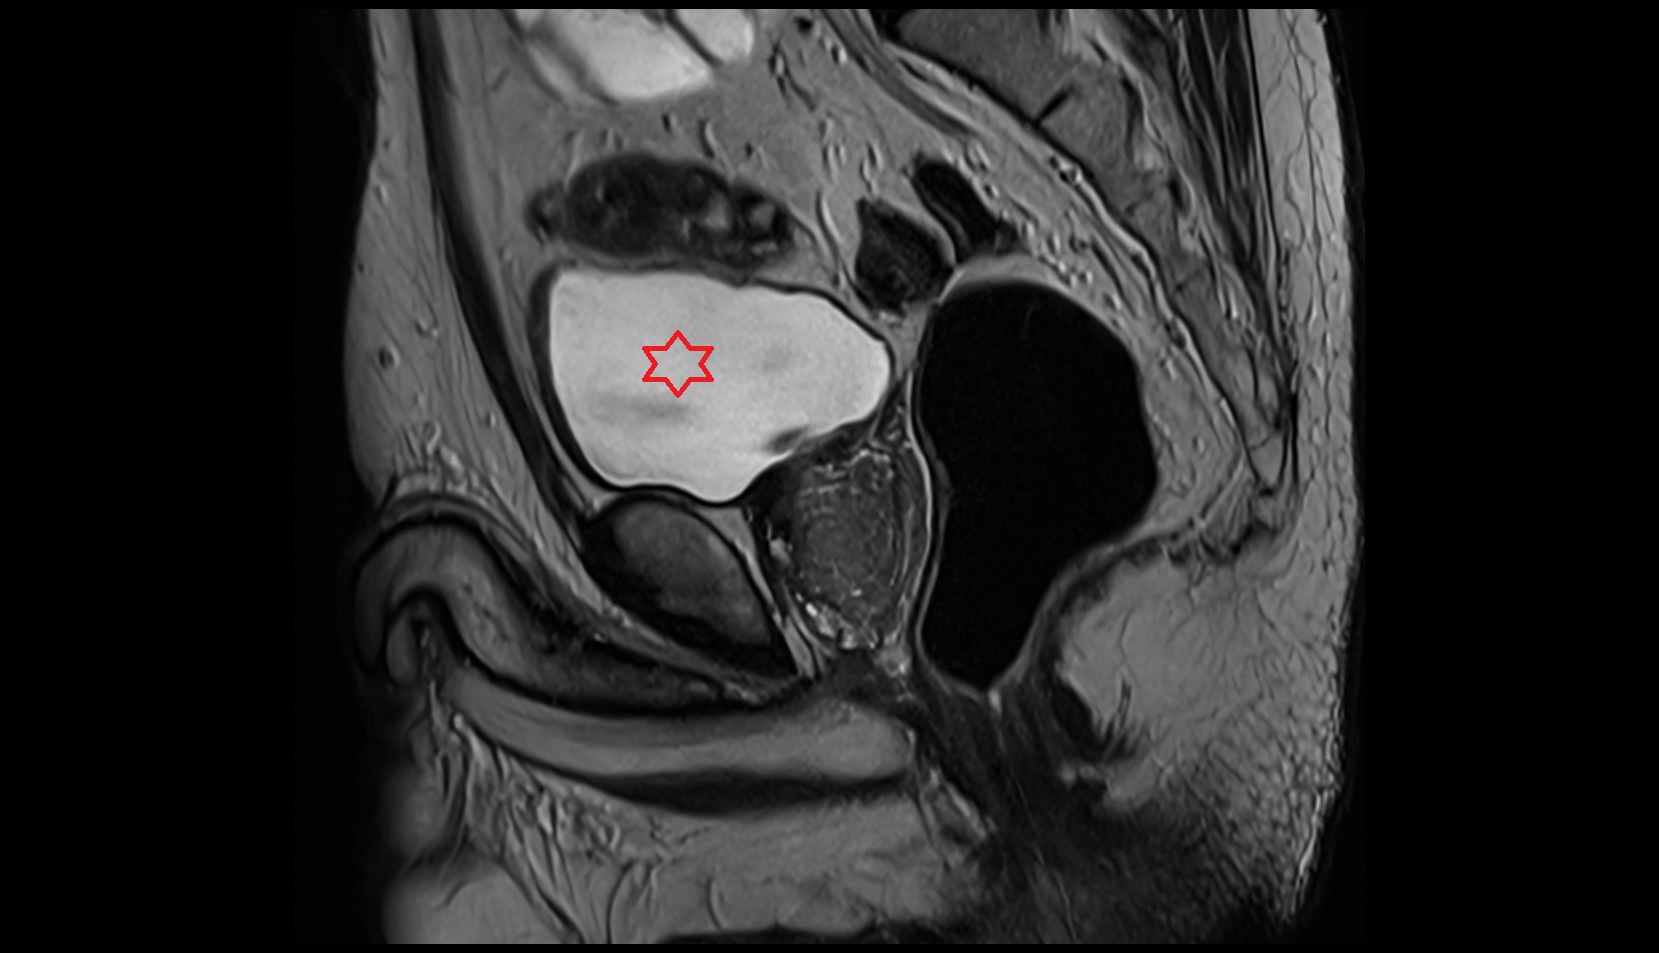

- Uterus

- Body of uterus

- Fundus of uterus

- Cervix of uterus

- Isthmus of uterus

- Endometrium of uterus

- Myometrium of uterus

- Perimetrium of uterus

- Junctional zone of uterus